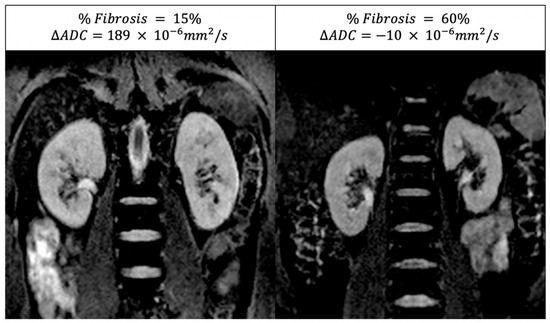

DWI-MRI indirectly estimates the amount of renal fibrosis and/or cellular infiltration. As fibrotic tissue reduces the motion of the water molecules, a decreased ADC may suggest higher fibrosis. In healthy kidneys, water diffusion is larger in the cortex than in the medulla; however, in DKD patients and those with other forms of CKD, ADC may be lower in the cortex than in the medulla due to fibrosis. As a result, the difference between the cortical and medullary ADC (called ΔADC) can be negative in the case of advanced fibrosis (see Figure 3). In analogy with BOLD-MRI, physiological parameters other than fibrosis (for example, renal perfusion and hydration status) may also influence the DWI signal and ADC values [29]. Therefore, DWI-MRI should be performed under standardised hydration conditions.

Figure 3. Example of an ADC map in two diabetic patients. On the left, the cortical ADC is higher (brighter) than the medullary ADC (positive Δ ADC = 189 × 10 6   mm 2 / s ) in a patient with a small amount of fibrosis (i.e., 15%) on the renal biopsy. On the right, the cortico-medullary ADC difference is lost (negative Δ ADC = 10 × 10 6   mm 2 / s ) in this diabetic patient with a higher amount of renal fibrosis on the renal biopsy (60%).